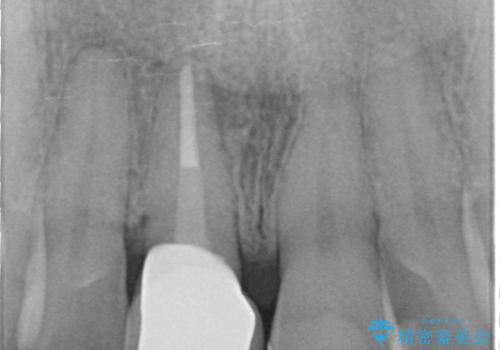

- 口の中に見える銀歯を、金属アレルギーの対策と審美性の向上のため全て除去したい!と希望され来院されました。

銀歯を丁寧に除去したのち、精度の良いセラミックインレー、セラミッククラウンで修復・補綴処置を行っていきます。

- 62.7万円(ジルコニアクラウン×3・仮歯×3・セラミックインレー×3)費用は治療当時の料金となります